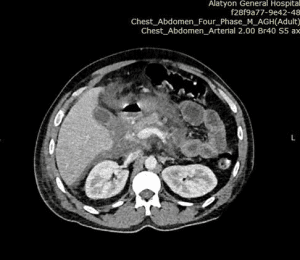

Before admission, he was initially imaged with abdominal ultrasound, and the visualization and detailed assessment of the pancreas was difficult because of a gaseous stomach. For this abdominal computed tomography (CT) scan with contrast, it shows that there is an enlarged pancreas head, neck, and uncinate process with heterogenous enhancement, stranding peripancreatic tissue with minimal peripancreatic fluid collection (Figure 2). We were not able to perform genetic tests for hyperlipidemia, due to the lack of access to the investigation and financial reasons.

Figure 2: Diffusely edematous pancreas with minimal peripancreatic fluid collection (white arrow)